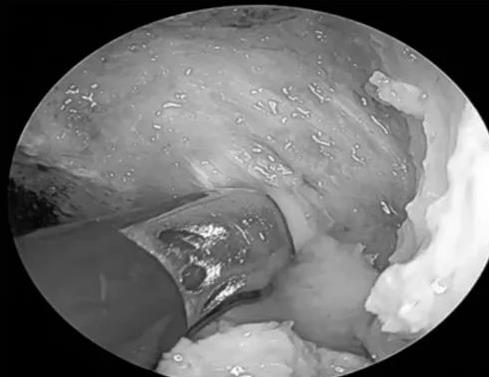

低温等离子行鼻咽部肿瘤切除术

早在2006年,红河州第三人民耳鼻咽喉-头颈外科在红河州率先引入低温等离子技术,在临床应用了16年,目前已广泛应用于儿童扁桃体及腺样体切除、鼾症的治疗,尤其在鼻咽部肿瘤、咽喉肿瘤以及早期喉癌治疗中的应用,通过选择合适的患者,进行低温等离子微创手术治疗,使手术更精准,恢复更快,减少局部损伤,促进早期康复,取得良好的临床治疗效果。

邓泽海副主任医师以《鼻内镜等离子下复发性鼻咽癌切除术、颅底粘膜瓣修复术》为题目,围绕肿瘤切除及颅底修复为主题,通过分享手术视频,详细向大家展示了局灶复发性鼻咽癌的手术切除过程要点及外科肿瘤手术切除理念(切缘阴性保证彻底切除病灶及修复重建)。